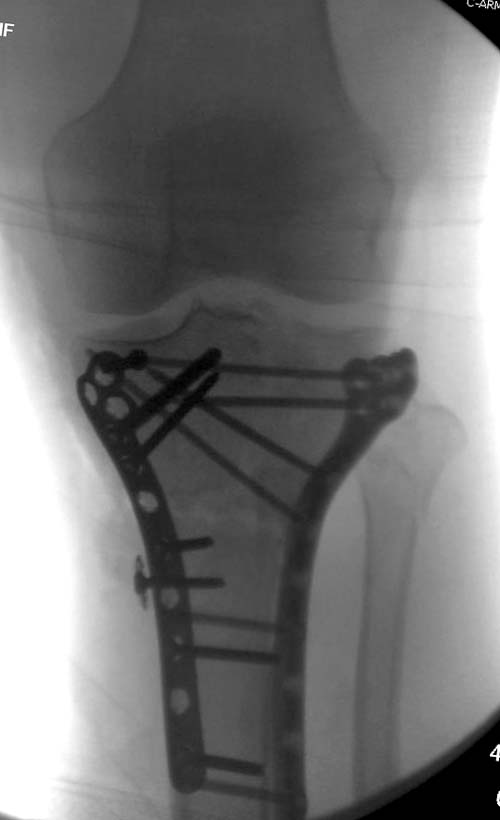

На боковом рентгене, явный задний смещенный компонент. КТ поможет увидеть "вершину" перелома, куда надо поставить антискользящую пластину из заднего или задне-медиальнего доступа. Для стабилизации боковой колонны традиционный боковой доступ через Girdle tubercle с длинной блокирующей пластиной. Одна задняя подпорка не удержит медиальную колонну, требуется длинная медиальная пластина.

Пластин для медиальной колонны не бывает, и поэтому подойдет любая тонкая пластина. Сегодня отходим от установки для тибиал плато толстых пластин, больше, чем 3.5 мм. Задача удержать, а нагрузка разрешается только после сращения в 3 мес., и поэтому нет смысла устанавливать толстые пластины

Перелом сложный, и для окончательного успеха потребуется арсенал фиксаторов и наличие опыта разных доступов. К успеху приведет только тщательное планирование. Возможно, фиксировать не удастся все за раз. Если во время операции возникнет опасность развития отека в ране, “damage control” операцию надо отложить, лучше поэтапно, чем осложнение.